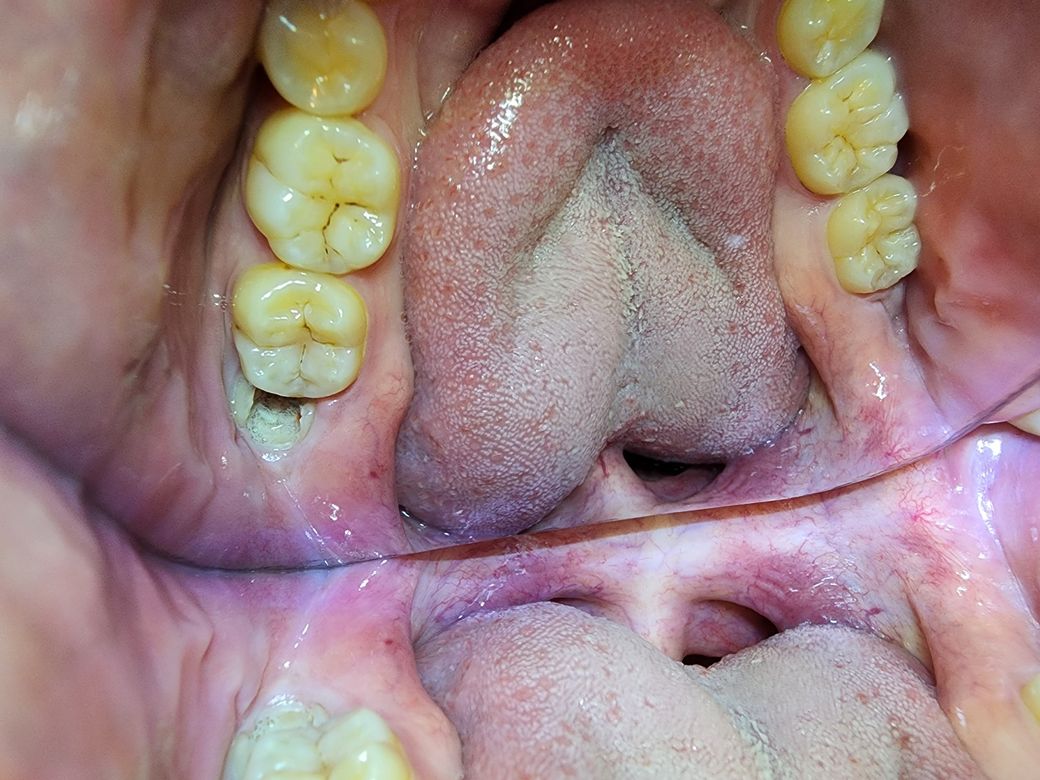

2015년 엑스레이 사진, 그리고 현재 2022년에 찍은 상악 1개 사진과 하악 2개 사진이에요.

현재 육안상으로 크게 문제가 있어보이는 곳이

- 상악에 송곳니? 근처에 썩은 이 하나.

이거는 제가 알기로는 저 어릴 때부터 안 뽑고 계속 가져왔던 것 같아요. 유치라고 하나요? 그래서인지 상악 치아 총 갯수가 홀수개에요.

상악에 유치 빼버리면 간단해보이는데 이걸 빼고나면 빈공간으로 다른 치아들이 자리잡을 것 같더라구요. 그런데 교정 비용을 대충 인터넷 검색해보니 몇백만원 나오는것 같아 경제적으로 좀 부담될것 같아서 고민이 됩니다. 지금 당장 통증은 없으니 이대로 그냥 살아갈지 아니면 어쩔 수 없으니 발치 후 교정치료까지 받아야할지 아니면 발치만 하고 교정은 안해야할지요..

현재 20번대 송곳니 뒤쪽으로 유치 송곳니가 남은것으로 보입니다. 해당치아가 충치가 심해서, 발치해야할 가능성이 높습니다.

만약 살릴 수 있다면, 신경치료, 포스트를 하여 살리는게 좋을 것으로 보입니다. 현재 치아가 한개 더 많은데, 이 상태로 치열이 배열되었기 때문에, 만약 이 치아를 발치한다면 교정을 하거나 임플란트를 해야하기 때문입니다.

상악에 썩어잇는 치아는 빼시고 임플란트를 하셔야될것같습니다. 저거 하나 빼고 교정하시는것보다는 빼고 임플란트를 하시거나 브릿지를 하시는게 더 좋을것같습니다. 그리고 사랑니는 썩어 잇으신거 같으니 발치를 하시는게 좋을것같아요.

왼쪽위에 4번째 치아는 충치가 많이 진행되어 신경이 노출된 상태이기 때문에 긴경치료를 동반한 보철치료가 필요합니다 .